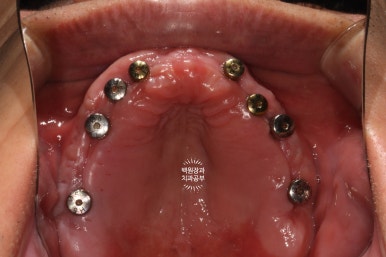

교합면에서 촬영한 사진입니다.

치아를 다 발치해야겠다는 생각이 절로 드는 환경이셨어요.

혹시나 보이시나 모르겠지만, 상당히 잇몸뼈가 얇음이.. 예상되는 상태였습니다.

이를 뽑고나서 임시틀니를 만들어드렸고, 위에서 보는 사진은 이를 제거 하고 약 1.5달 뒤 사진입니다.

잘 보시면, 이를 뽑고나서 잇몸이 잘 아물어 단단한 잇몸이 되어 있는 것을 보실 수 있으실거에요.

그리고 계획한 대로 임플란트에 긴 뚜껑을 껴주게 되는데요,

바꿔서 껴드린 이 뚜껑을 치과에서는 치유지대주 (healing abutment)라고 부르고, 잇몸이 아물게 되면 이제 보철치료를 시작할 수 있습니다. 약 1-2주 정도 기다리게 됩니다.

이렇게 위에는 8개의 임플란트가, 아래에는 6개의 임플란트가 예쁘게 식립된 것을 보실 수 있을겁니다.